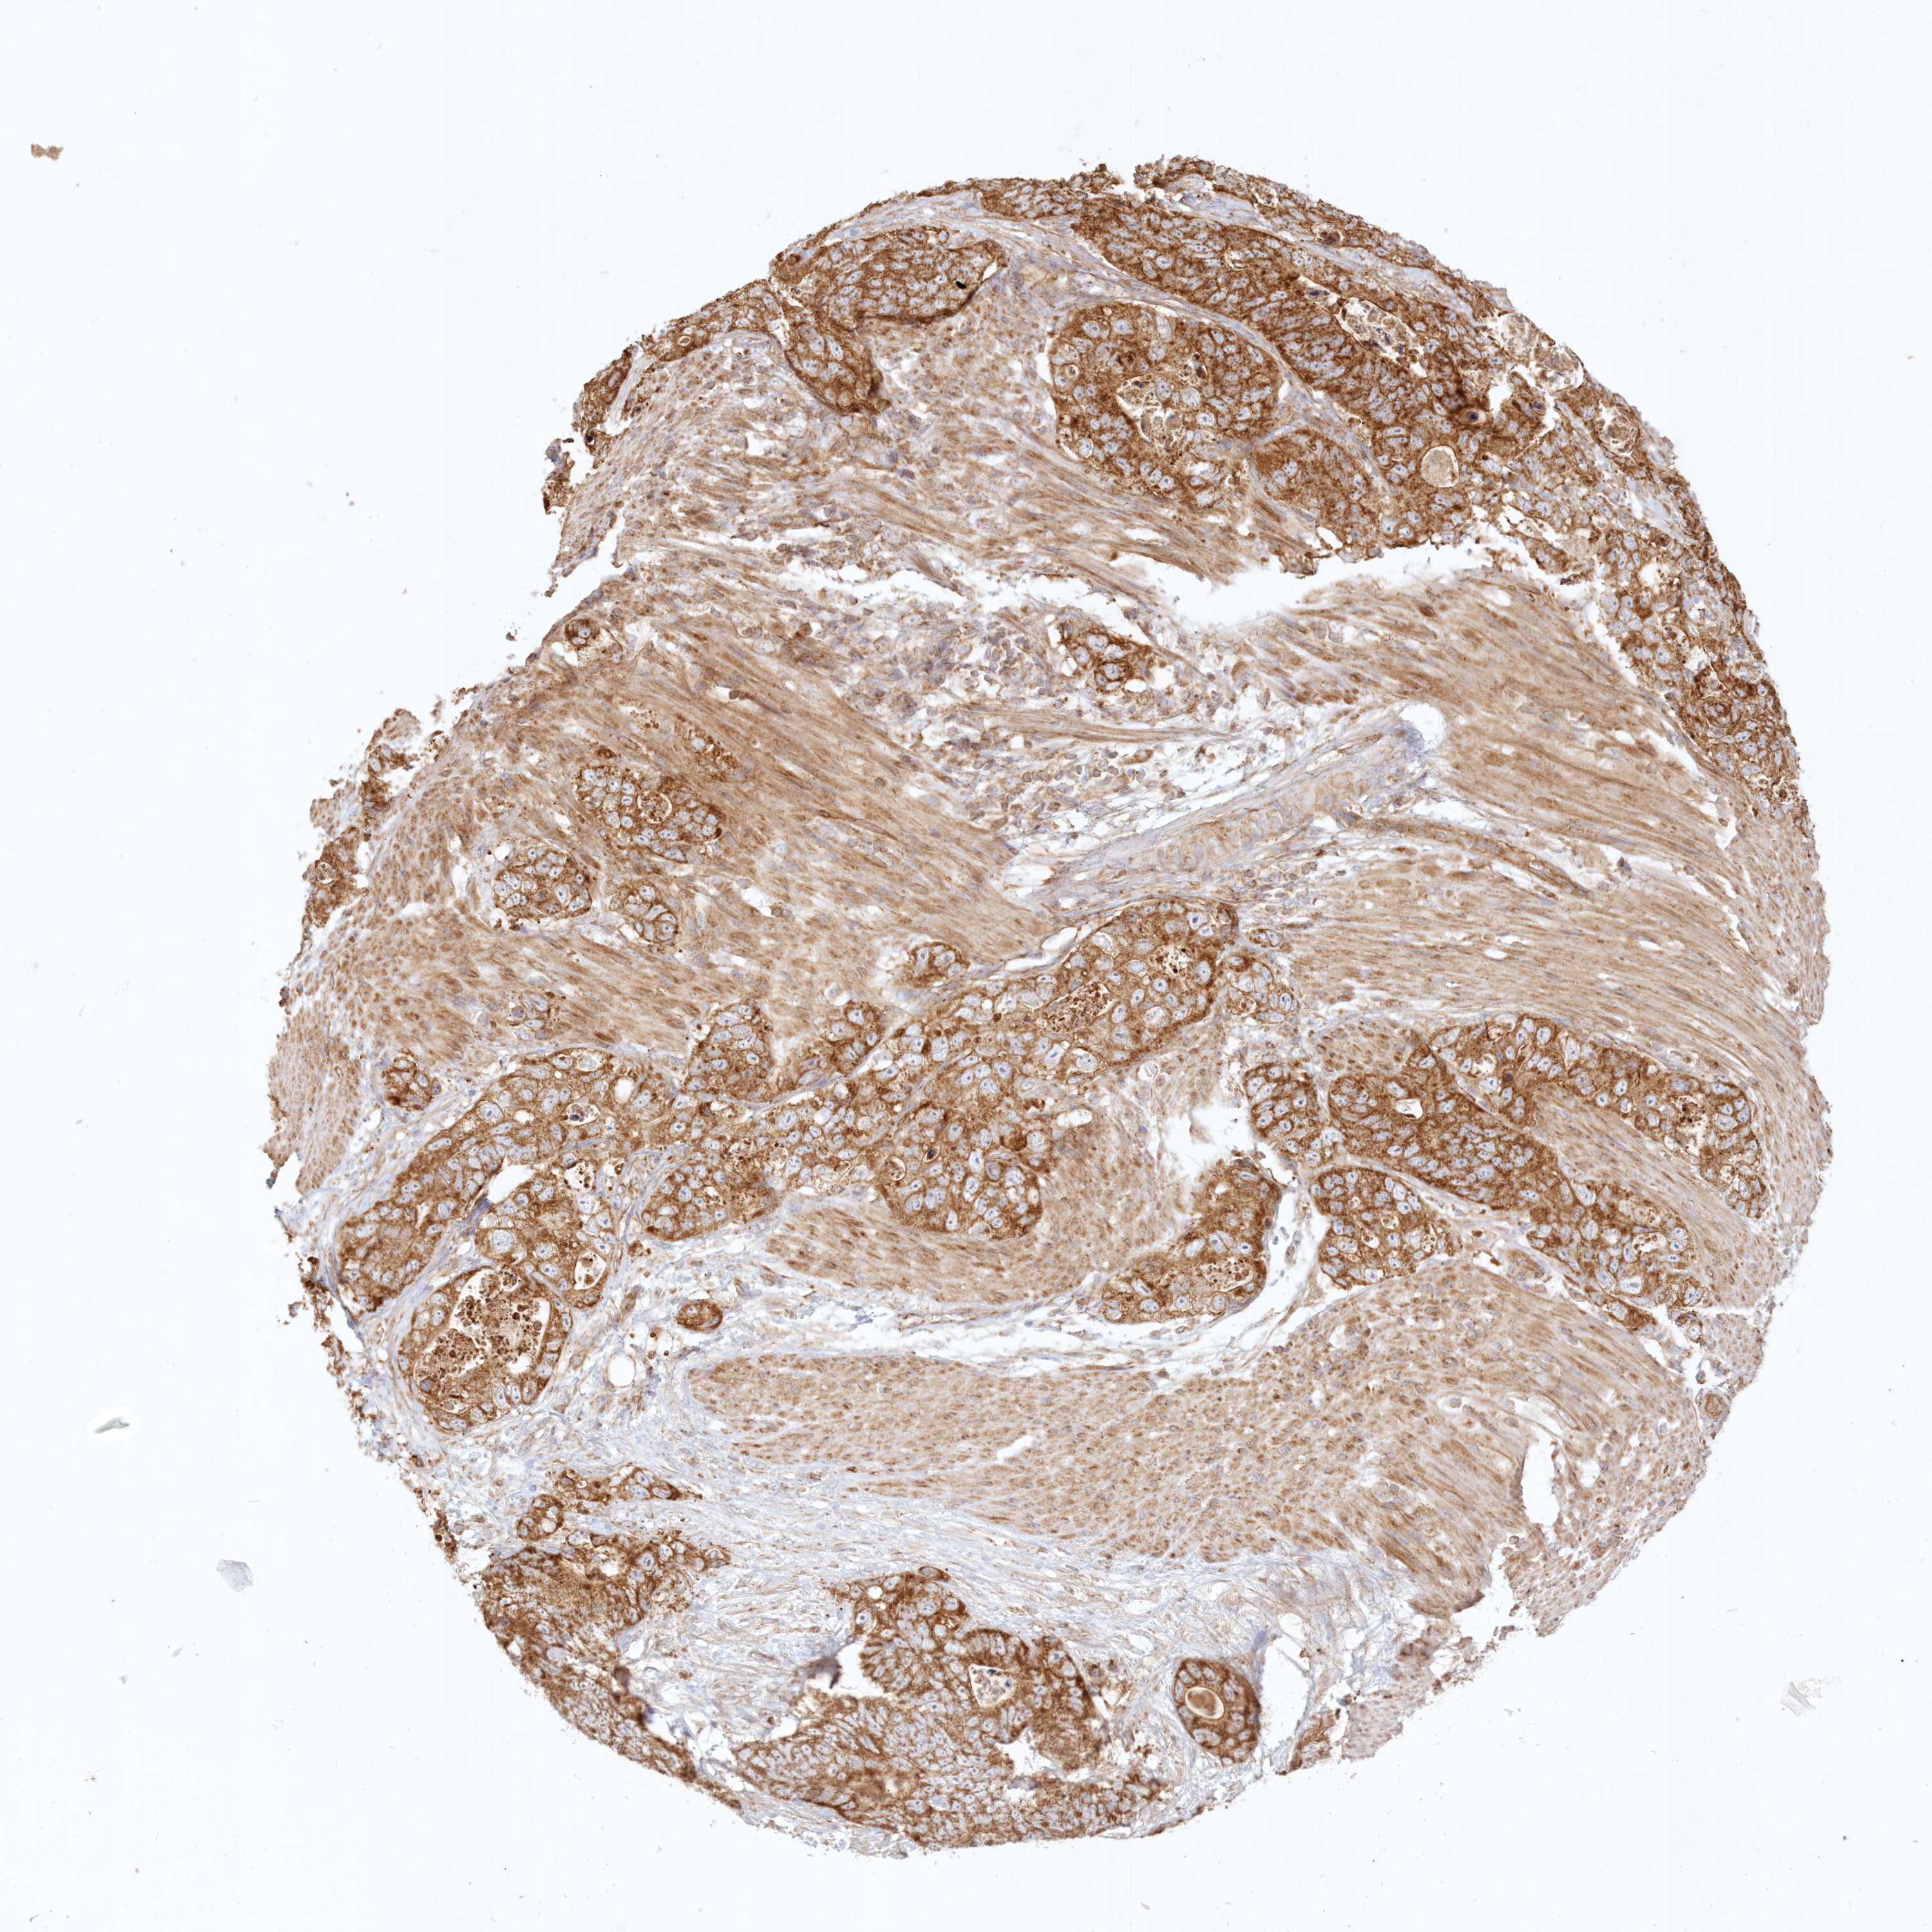

STOMACH CANCER - Protein expressioni

A mouse-over function shows sample information and annotation data. Click on an image to view it in a full screen mode. Samples can be filtered based on level of antibody staining by selecting one or several of the following categories: high, medium, low and not detected. The assay and annotation is described here.

Note that samples used for immunohistochemistry by the Human Protein Atlas do not correspond to samples in the TCGA dataset.

Antibody stainingi

Antibody staining in the annotated cell types in the current human tissue is reported as not detected, low, medium, or high, based on conventional immunohistochemistry profiling in selected tissues. This score is based on the combination of the staining intensity and fraction of stained cells.

Each image is clickable and will lead to virtual microscopy that enables deeper exploration of all samples and also displays staining intensity scores, fraction scores and subcellular localization as well as patient and tissue information for each sample.

Antibody HPA036891

Antibody HPA036892

Antibody HPA061498

Staining

High

Medium

Low

Not detected

Intensity

Strong

Moderate

Weak

Negative

Quantity

>75%

75%-25%

<25%

None

Location

Nuclear

Cytoplasmic/membranous

Cytoplasmic/membranous,nuclear

Adenocarcinoma, NOS